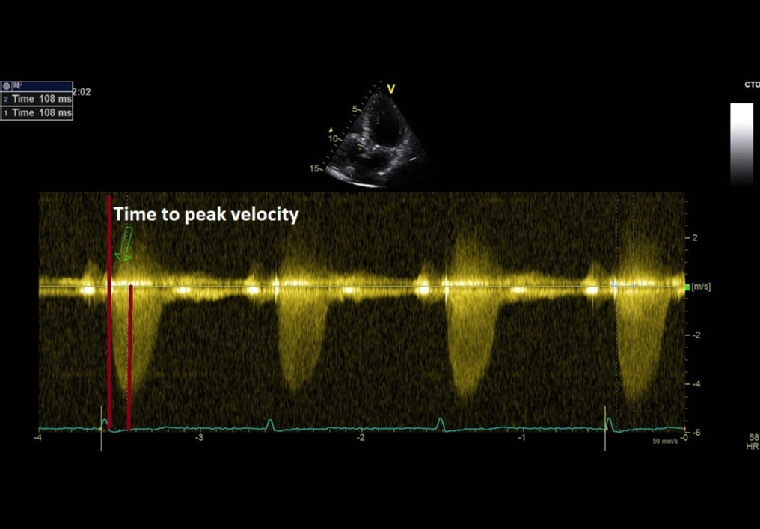

As aortic stenosis worsens, it takes longer for blood to be ejected through the valve. Thus, mild AS would have an early peaking murmur, while in severe AS the murmur peaks later in systole. Even if it is a highly specific clinical sign for severe AS, the evaluation of the timing of the murmur has a very low reproducibility among examiners. Derived from this clinical finding, time-to-peak-velocity (TPV) is a new echocardiographic variable that is easily measured, reproducible and useful to evaluate AS severity (Figure 1). In the study of Kamimura et al, a TPV cut-off value of 99 msec had the highest sensitivity, specificity, and positive and negative predictive values in detecting severe AS (irrespective of ejection fraction) and also for predicting a poor prognosis in AS patients [11].

209_Siliste_Figure 1_Physical examination in aortic valve disease do we still need it in the modern era.jpg